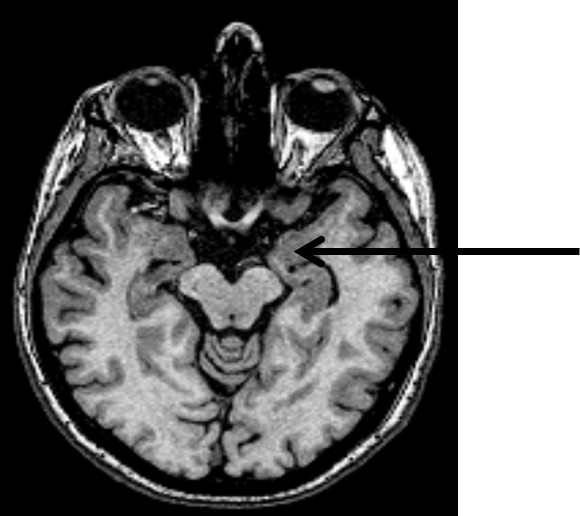

Struktura wskazana strzałką na obrazie MR mózgu to: